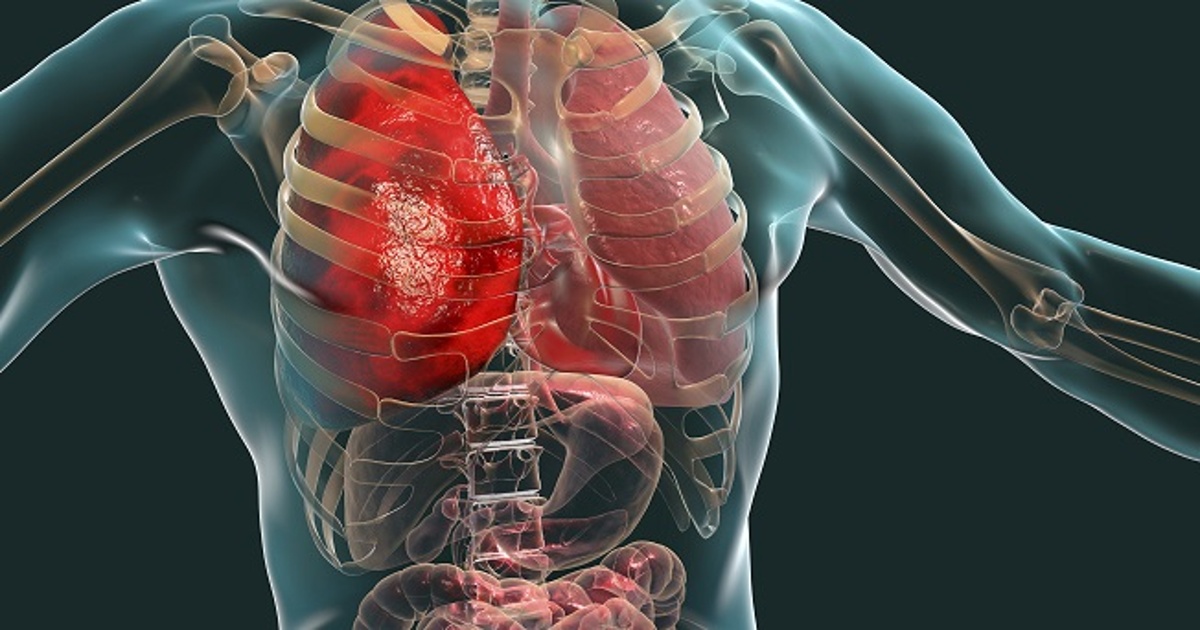

There was a time when organ failure was mostly associated with old age. Today, however, rising organ failure in young patients is becoming a heartbreaking reality across hospitals worldwide. Teenagers, college students, young parents in their 20s and 30s — many are now battling severe kidney and liver failure, urgently needing transplants to survive.

The Kidney Transplant Demand Is Surging

The Liver Transplant Crisis: A Race Against Time

Organ Donation Awareness: At the heart of rising organ failure in young patients lies a sobering truth—organ donation rates remain critically low in many regions.

A Moral and Medical Imperative

The growing wave of rising organ failure in young patients is a wake-up call. It challenges us to rethink healthcare systems, community responsibility, and preventive habits.